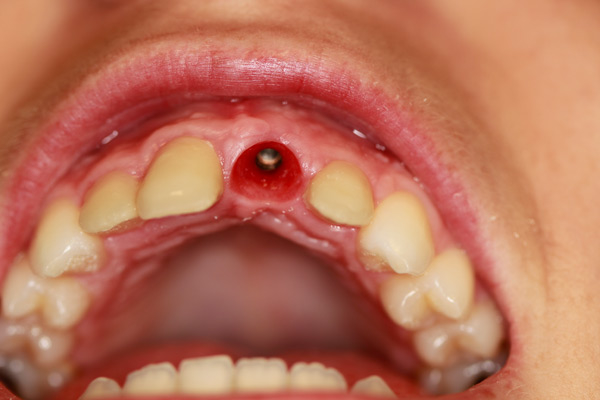

Case Study 7

Problem: This young patient lost her front tooth. She also had a dark tooth that was treated with a root canal.

Plan: Our plan… placed an implant then molded the tissue for a few months to get the best appearance. A zirconium abutment was used to restore the tooth and veneers on the other three front teeth.

Creating beautiful smiles.